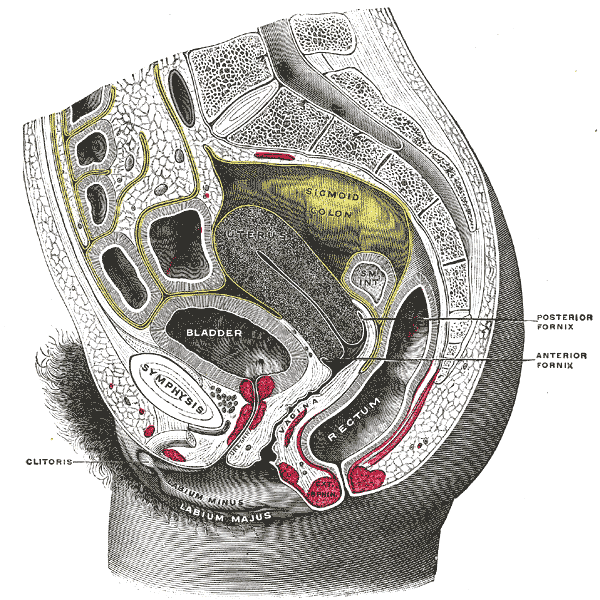

Normal Gynecologic Anatomy

anatomy #1